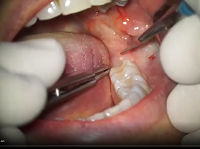

Oral Suergery (Zerodonto Dentistry) 2018

Spécialités : Stomatologie